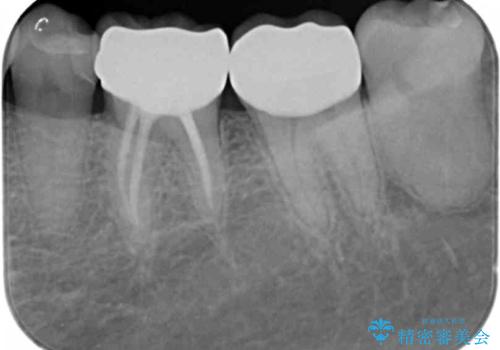

残っている歯を削らないよう、丁寧に除去したのち精密なジルコニアセラミッククラウンで再咬合構成を行っていきます。

見た目の改善が達成できたとともに、皮膚のかゆみも明らかに減少したと喜んでいただくことができました。